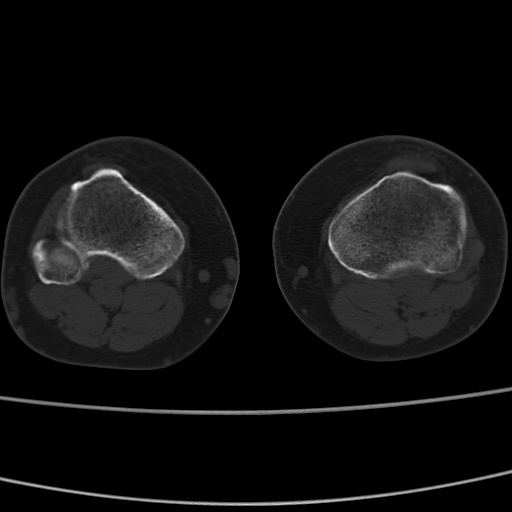

女性,50岁。【请提供患者临床症状体征】

胫骨后缘陈旧性骨折(是否有病史)

右膝关节退行性改变,关节游离鼠。

右膝关节退行性改变,滑膜黏液囊钙/骨化并游离。